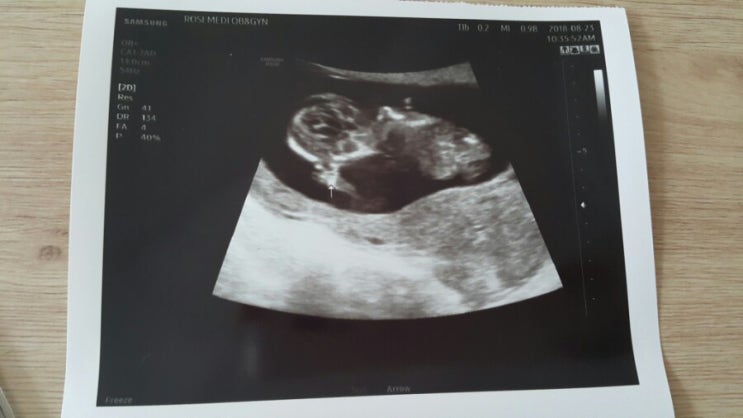

[임신기록]임신20주.정밀초음파

안녕하세요 아무생각없이 정기 검진 기간이라 병원에 갔는데 몸무게는 임신 초기보다 5kg이나 찌고 혈압은 ...